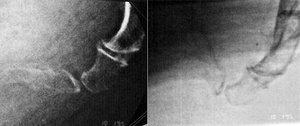

Hypermobility of the coccyx (greater than 25 degree change of angle between standing and sitting). Images reprinted with permission from Jean Yves Maigne, MD.

The second is hypermobility: a coccyx segment that has more than 25 degrees of motion (usually into flexion), comparing the standing film to the sitting film. Both of these findings represent excessive motion. The pictures below show these findings.

When you have either of these findings on the dynamic coccyx X-ray, you know there has been significant anatomical damage to the coccyx. In either of the above scenarios (dislocation or hypermobility), the ligaments are quite likely to be damaged and lax. I have talked a lot about functional hypermobility over the past few years. Here is a place where we can see and measure anatomical hypermobility. If the patient has excessive coccyx motion, it means something damaged those ligaments. This is a very small set of bones and ligaments which can be easily traumatized in a fall.